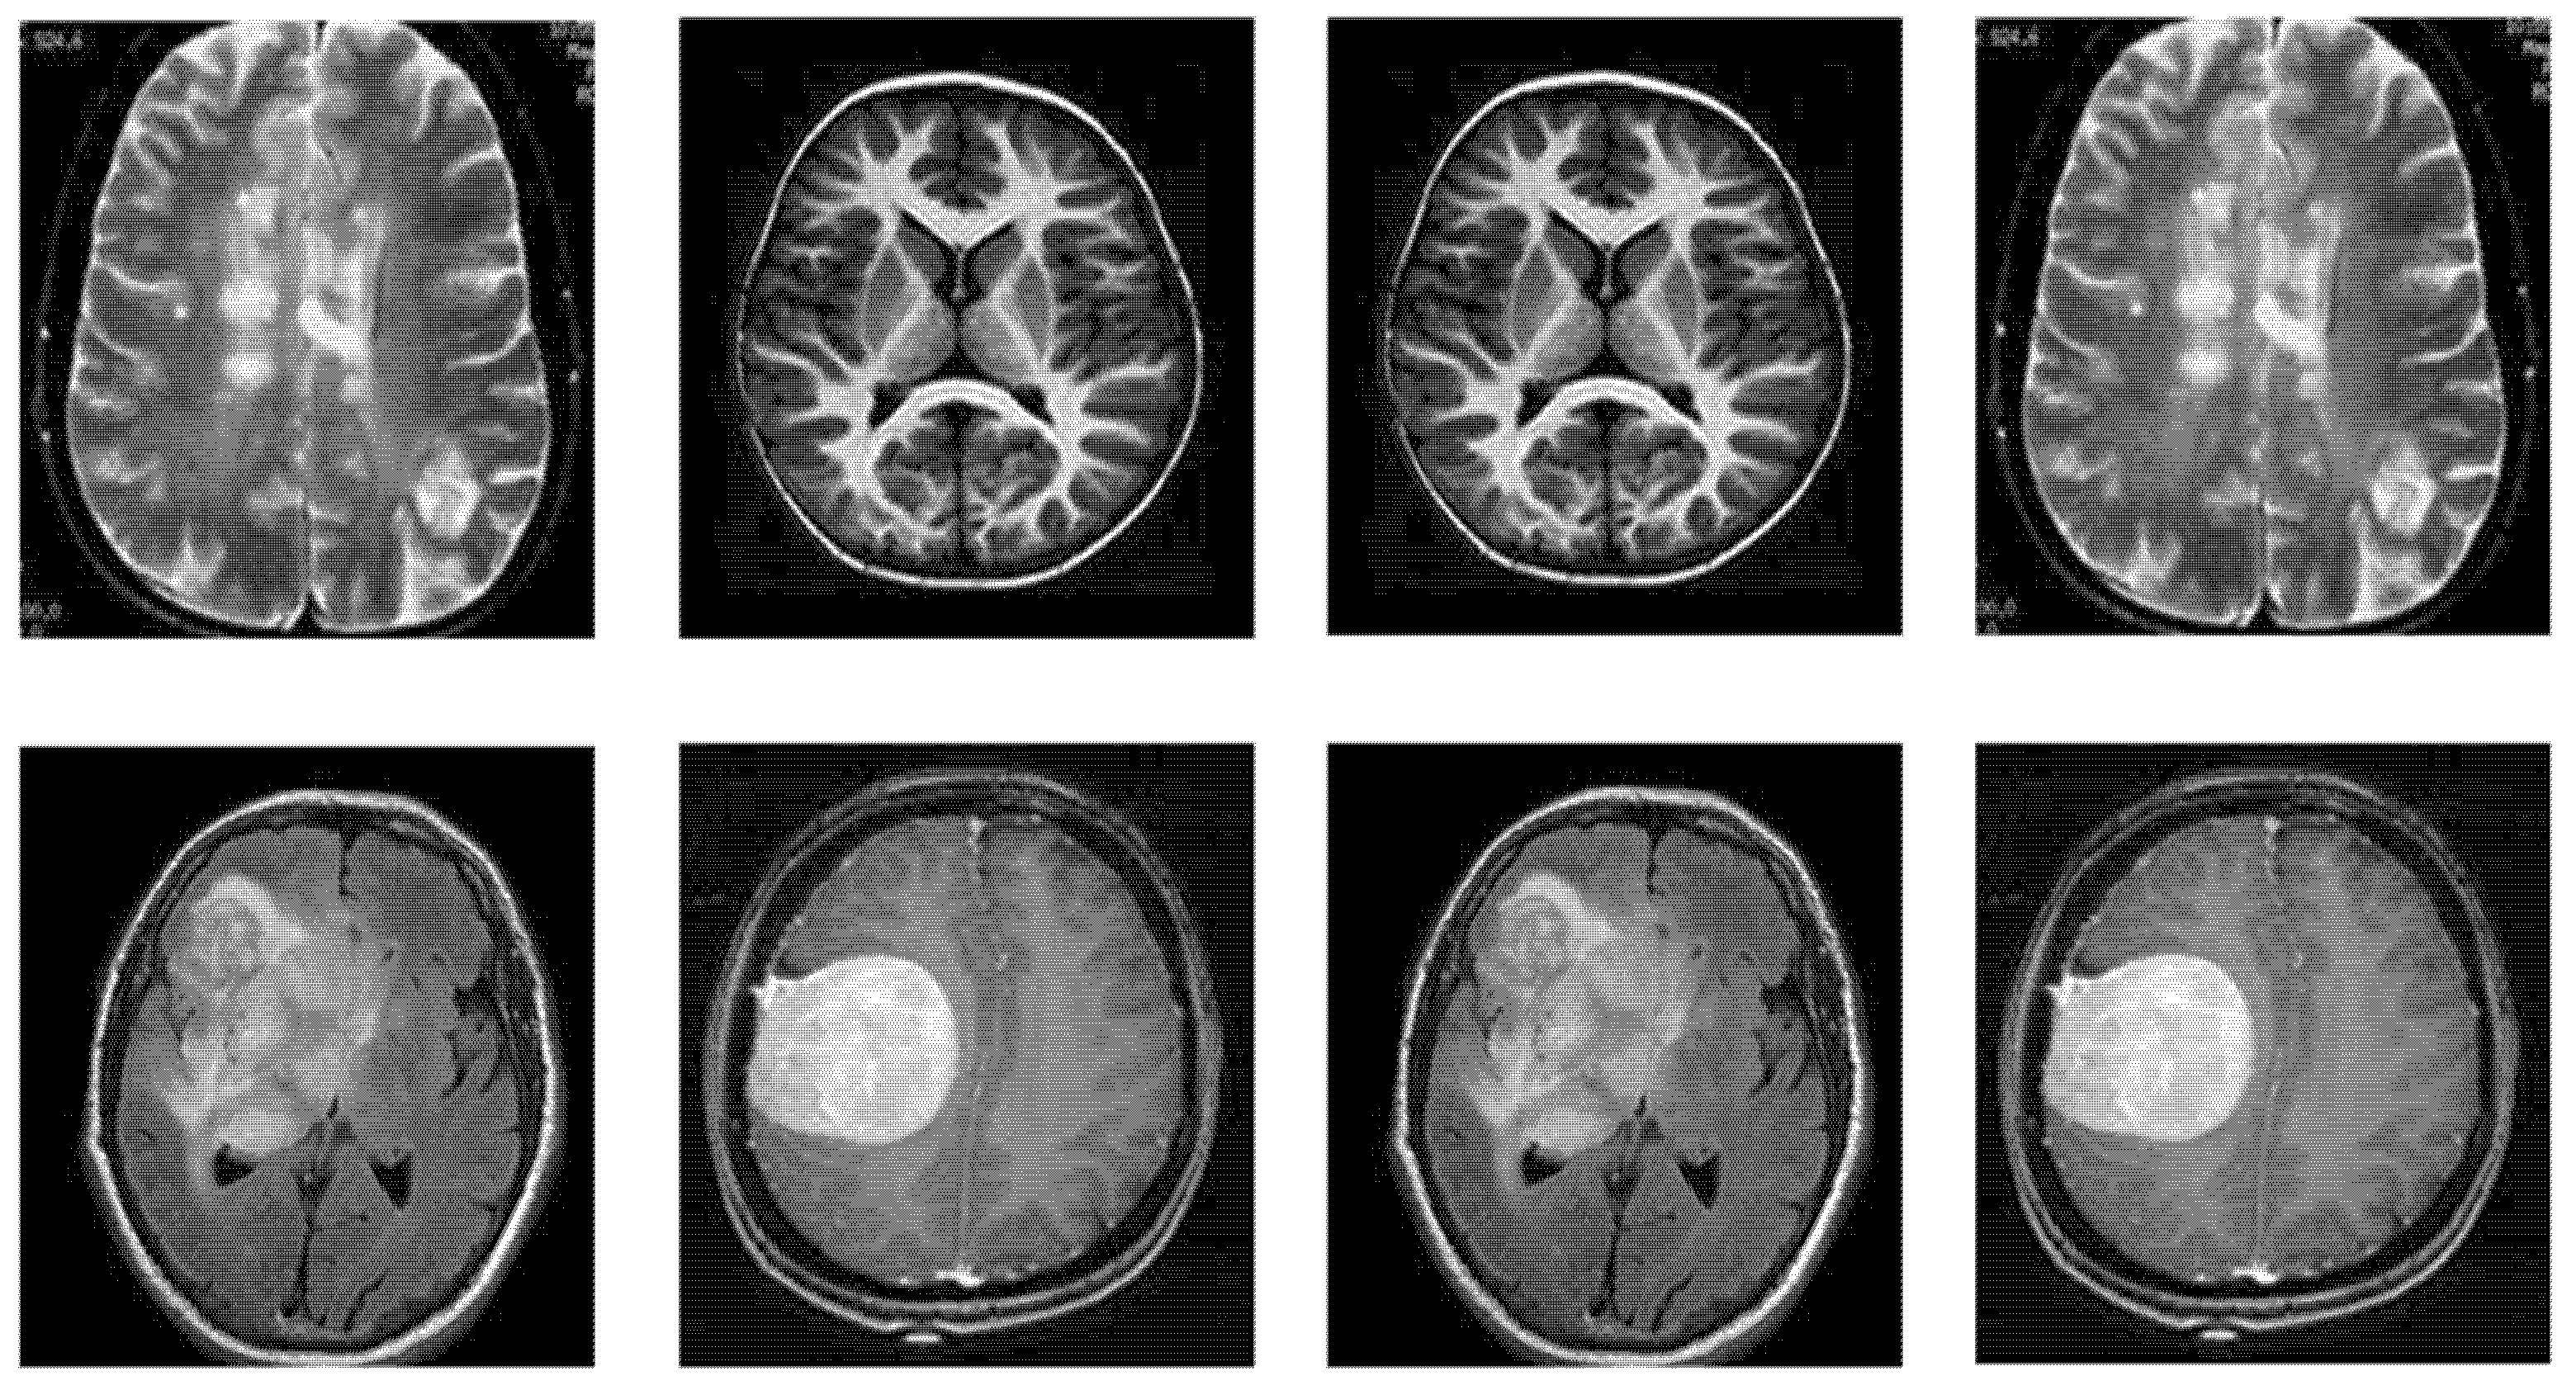

4.2. Dataset

This section includes comprehensive details regarding the dataset utilized for BTD. The research dataset utilized for detecting brain tumors in this study is adopted from the BTD-MRI dataset, which is easily accessible on Kaggle [31]. The dataset comprises two collections. The first collection of the dataset has 1500 MRI images without tumors, whereas the second collection has 1500 tumor images. We used 80% of the data for training and 20% (remaining) for testing the TumorResNet model. More specifically, we used all 3000 images of the standard Kaggle BTD-MRI dataset [28] for this experiment, where 2400 images (1200 tumorous and 1200 healthy images) were utilized for model training and the rest 600 images (300 tumorous and 300 healthy images) for testing. Some representative samples from the dataset are shown in Figure 2.

Figure 2. Samples of BTD-MRI dataset, upper row: No tumor examples and lower row: tumorous images examples.